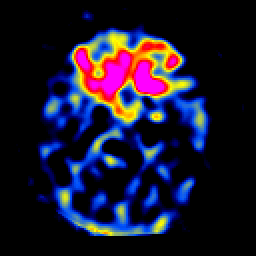

SPECT TL Study #6 -- Slice #20